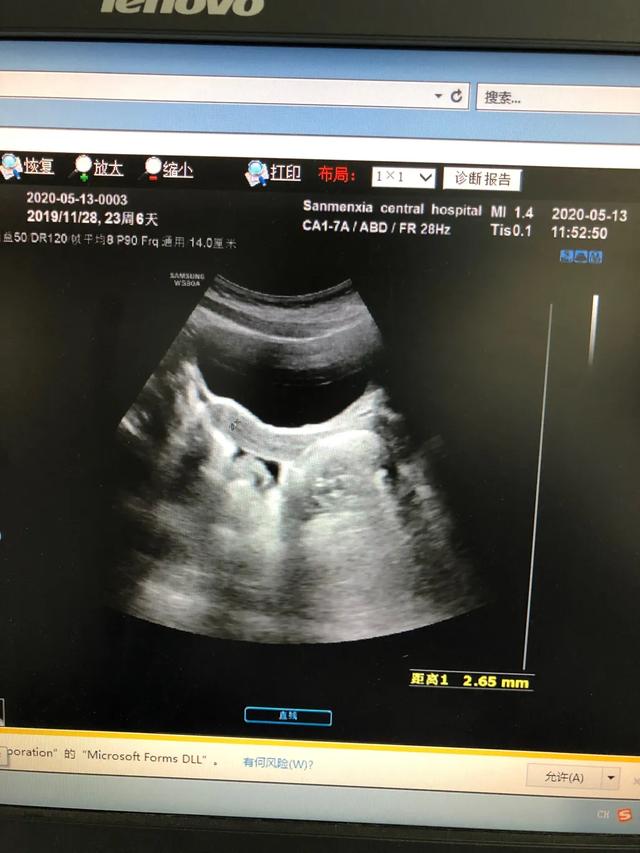

下图是一例患儿性早熟的B超结果、胸片结果及血清学化验结果。

从检查结果来看,B超显示子宫卵巢有囊性回声;胸片显示乳腺发育;而血清学指标,促黄体生成素的峰值是13.09,促卵泡的峰值是20.91,LH/FSH=62.60%。